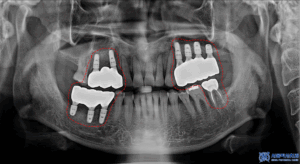

더 정밀히 확인하기 위해,

엑스레이 사진을

찍어보았습니다.

왼쪽 아래 사랑니를 포함한 큰어금니는

맞닿는 위 치아가 없어

정출되어 있는 상황이였고

왼쪽 위는 치아가 없을 뿐 아니라

골흡수가 심하게 진행되어

상악동과의 거리가 가까워져

뼈가 부족한 상황이었습니다.

또한 오른쪽 위 어금니들 역시

치아를 지탱하는 잇몸뼈가

많이 흡수되어 있는 것이

확인되었습니다.

임플란트 식립을 위해서는

3D CT 사진을 촬영하여

더 자세히 보아야 하는데요.

평면적인 사진과 같이

뼈가 많이 녹아있는 것을

볼 수 있습니다.